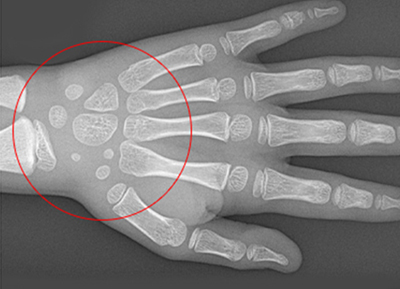

손으로 확인하는

우리아이 성장판 검사

아이의 나이 만으로 발육 정도를 파악 할 수 있지만 동일한 나이임에도 불구하고

개인적인 성숙도가 많이 다르기 때문에 정확한 성장 정도를 판단하기 위해 성정판 검사를 통해 교정의 적절한 시기를 결정합니다.

• 1

열려있는 성장판

• 2

닫혀가는 성장판

• 3

완전히 닫힌 성장판

성장판이 닫혀 있어도 치아 교정이 가능하지만 골격적인 부분에 대한

교정이 이루어 지려면 성장판이 닫히기 전에 교정을 시작하여야 더 좋은 효과를 기대할 수 있습니다.